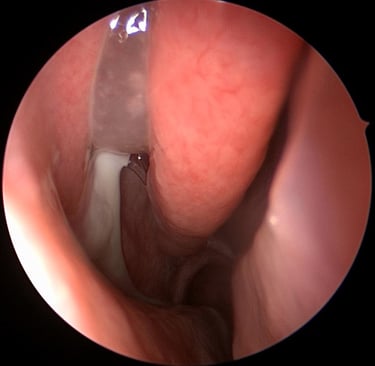

visão endoscópica Sinusite